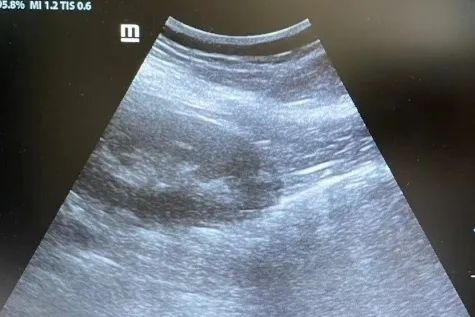

腹腔镜下肾穿刺后肾周无明显血肿